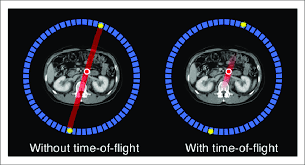

What is the new technology in PET that allows us to get an idea of where an annihilation event happened on the line of response?

Time of flight technology

What is time flight technology?

Where the new technology allows us to better determine where an annihilation event happened based on how soon (time) the photon hit the detector – i.e. it taking 0.5 seconds for the right side vs. 1.5 seconds for the left side → annihilation most likely happened more on the right

How does time flight technology affect how our images on PET turn out?

It decreases our need for having multiple line of responses – able to use shorter line of responses and get rid of all the bad and excess information that makes the images less clear – better able to focus on what we intend to image

How does time flight technology affect how we dose and image the patient in PET?

If we’re able to eliminate bad information using the new technology, we won’t need to overcome the bad information with good information – able to give less of a big dose and not need to image as long